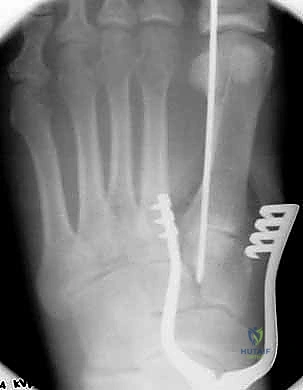

1. الرد المفتوح والتثبيت الداخلي (ORIF - Open Reduction and Internal Fixation)

هذا هو الإجراء الكلاسيكي والأكثر شيوعاً. يهدف إلى إعادة العظام إلى مكانها الطبيعي (الرد) وتثبيتها باستخدام معدات طبية (مسامير، شرائح، أو أسلاك) حتى تلتئم الأربطة والعظام.

خطوات العملية:

1. التخدير: يتم إجراء الجراحة تحت التخدير الموضعي (النصفي) أو العام.

2. الشق الجراحي: يقوم الدكتور هطيف بعمل شق جراحي دقيق (أو شقين) على ظهر القدم للوصول إلى المفاصل المصابة، مع الحرص الشديد على حماية الأعصاب والأوعية الدموية الدقيقة في تلك المنطقة باستخدام مبادئ الجراحة المجهرية.

3. التنظيف والرد: يتم تنظيف المفاصل من أي شظايا عظمية أو أنسجة محشورة تمنع عودة العظام لمكانها. ثم يتم إعادة العظام بحذر شديد إلى محاذاتها التشريحية الدقيقة (القوس الروماني).

4. التثبيت (Fixation): يتم تثبيت العظام باستخدام مسامير معدنية خاصة (Solid or Cannulated Screws) تعبر المفاصل لتثبيتها بإحكام. في بعض الحالات، يتم استخدام شرائح معدنية صغيرة للحفاظ على الاستقرار.

5. مسمار ليزفرانك: الخطوة الأهم هي وضع "مسمار ليزفرانك" (Lisfranc Screw) الذي يمر من العظم المسماري الإنسي إلى قاعدة المشط الثاني، لتعويض وظيفة الرباط الممزق.

6. الإغلاق: يتم إغلاق الشقوق الجراحية بعناية تجميلية ووضع القدم في جبيرة لحمايتها.